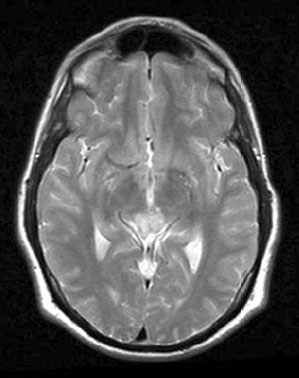

Fig.

5 (March, 2003)